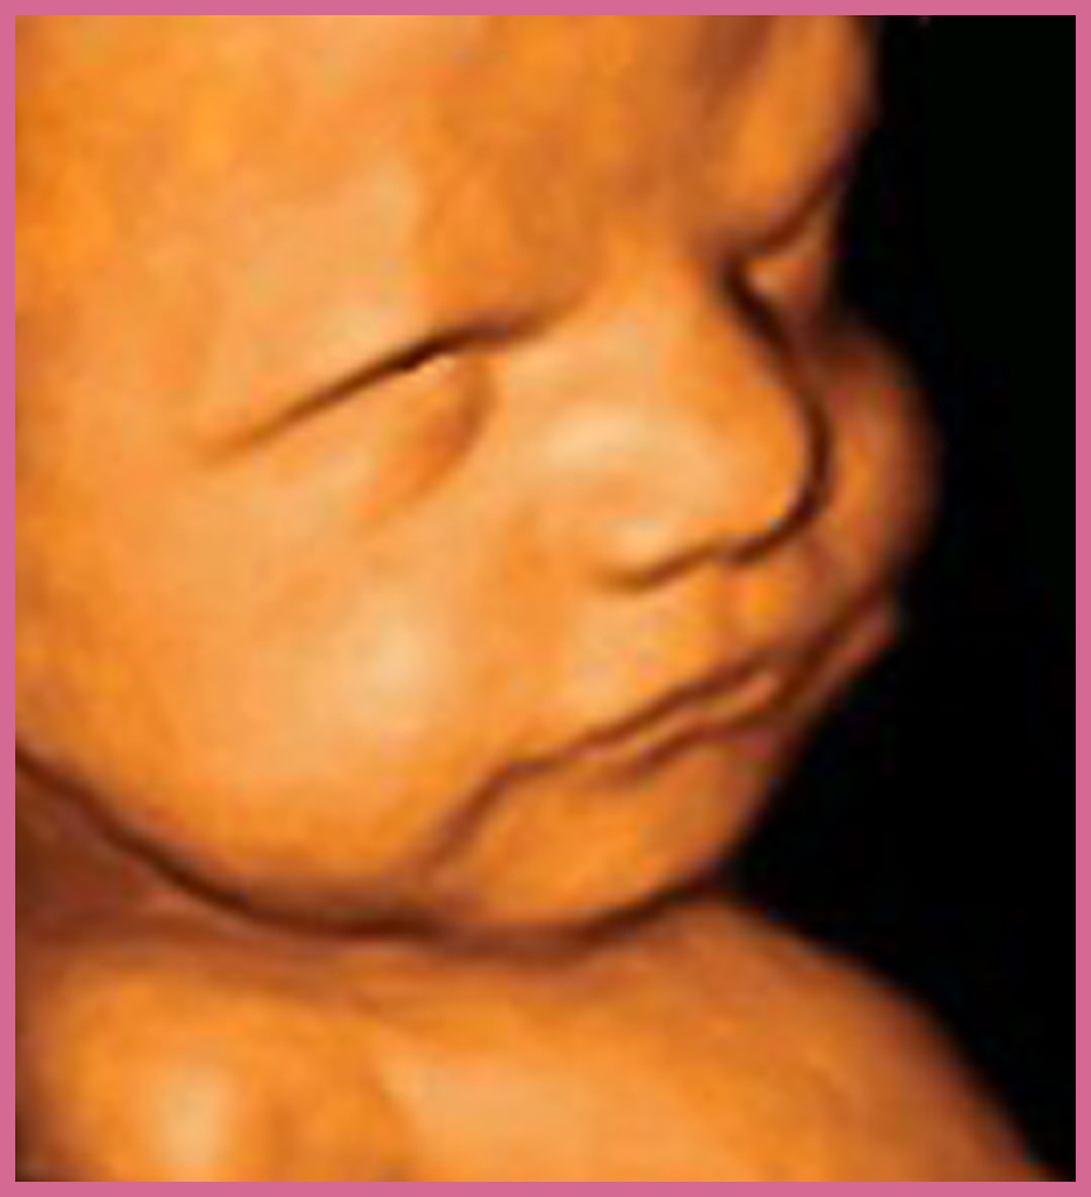

Il pancione è cresciuto ancora e non permette di vedere neanche i piedi. Il bambino pesa circa 2 kg ed è lungo circa 38 cm. Ogni settimana metterà su tra i 200 e i 250 gr e diventerà sempre più cicciottello. Le ossa cominciano a solidificarsi, esclusa la scatola cranica, che deve rimanere malleabile per permettere la nascita.

Il piccolo continua a crescere e dovrebbe pesare circa 2250 grammi, ma le stime del peso fetale sono variabili e oscillano di circa il 10% in più o in meno a quanto segnalato. Infatti, ora ci si basa su dei calcoli di equazioni matematiche partendo dalle misure ecografiche della circonferenza cranica, della circonferenza addominale e della lunghezza del femore che possono orientare sul peso, ma non darne la certezza.

Il peso del piccolo è arrivato intorno ai 2550 gr., è più rotondo, si muove in rapporto al poco spazio che ha a disposizione e il suo sistema neurologico è ben sviluppato.

Il bambino è arrivato a pesare circa 2750 grammi ed è lungo circa 48 centimetri. Il suo corpicino comincia a perdere la peluria e la vernice caseosa che l’ha ricoperto finora per proteggerlo dall’azione irritante del liquido amniotico. Queste e altre sostanze sono ingerite dal piccolo con il liquido e vanno a formare il meconio.